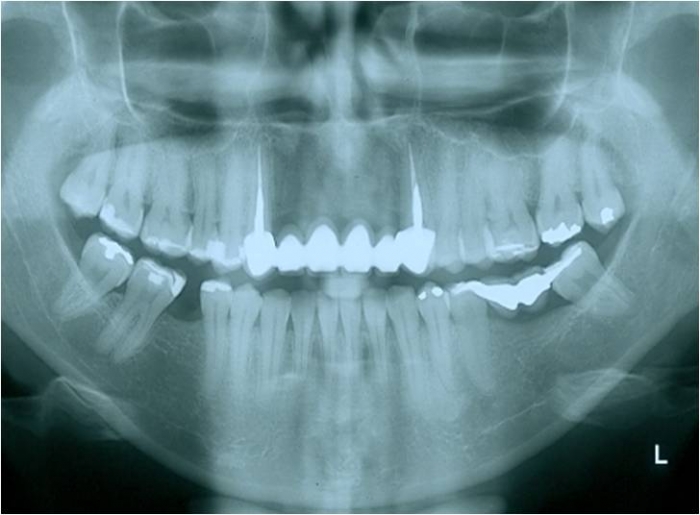

Raio x após enxerto ósseo